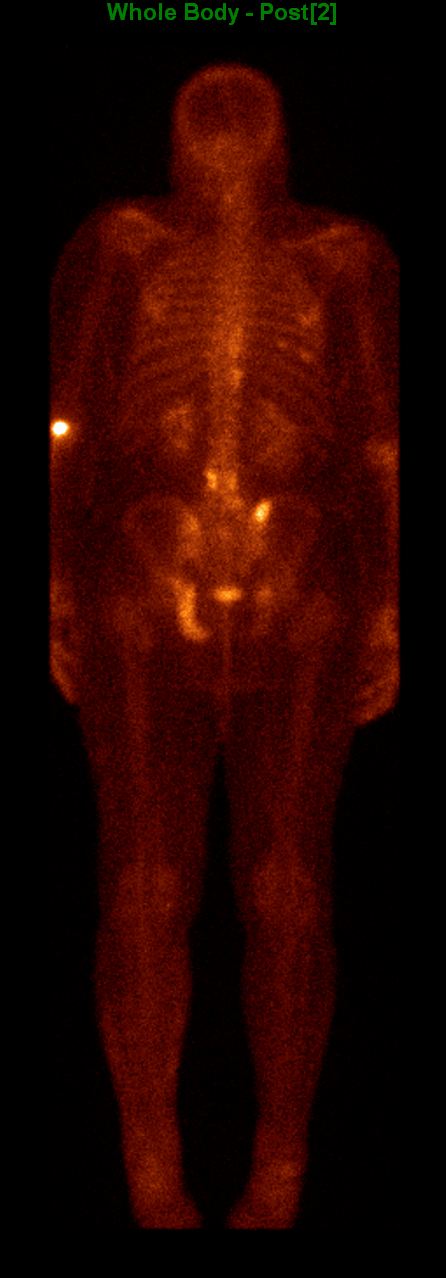

Among the general characteristics of isotope examinations, besides the ability to gain functional information, it is important to mention that – derived from the tracer principle – the examinations are highly sensitive, so the pathological processes can be detected at an early stage. SPECT is able to detect nano-molar radiotracer concentrations, while PET picks up signals coming from pico-molar radiopharmaceutical quantities. The higher sensitivity is due to the fact that functional alterations of metabolism usually precede detectable morphological changes of the tissues, thus functional studies allow earlier and more precise diagnostics. Another aspect of higher sensitivity is that in an optimal scenario, the biologic contrast between normal and pathologic function is very high. Therefore, signal intensity of a normal tissue process will be much lower than that of a pathologic one, making them easily distinguishable on the image. (Figure 2.)

Test iframe

2. FDG PET Maximum Intensity Projection (MIP) image. There is a large biological contrast between the normal and the pathologic tissues. Right sided breast cancer, ipsilateral metastatic lymph nodes and multiplex metastases in the lung. Physiologically elevated FDG uptake is seen in the brain, salivary glands, tonsils, liver and the spleen as well as in the bone marrow and at certain segments of the intestines. Also, there is increased FDG activity in the kidneys and the urinary bladder due to excretion.